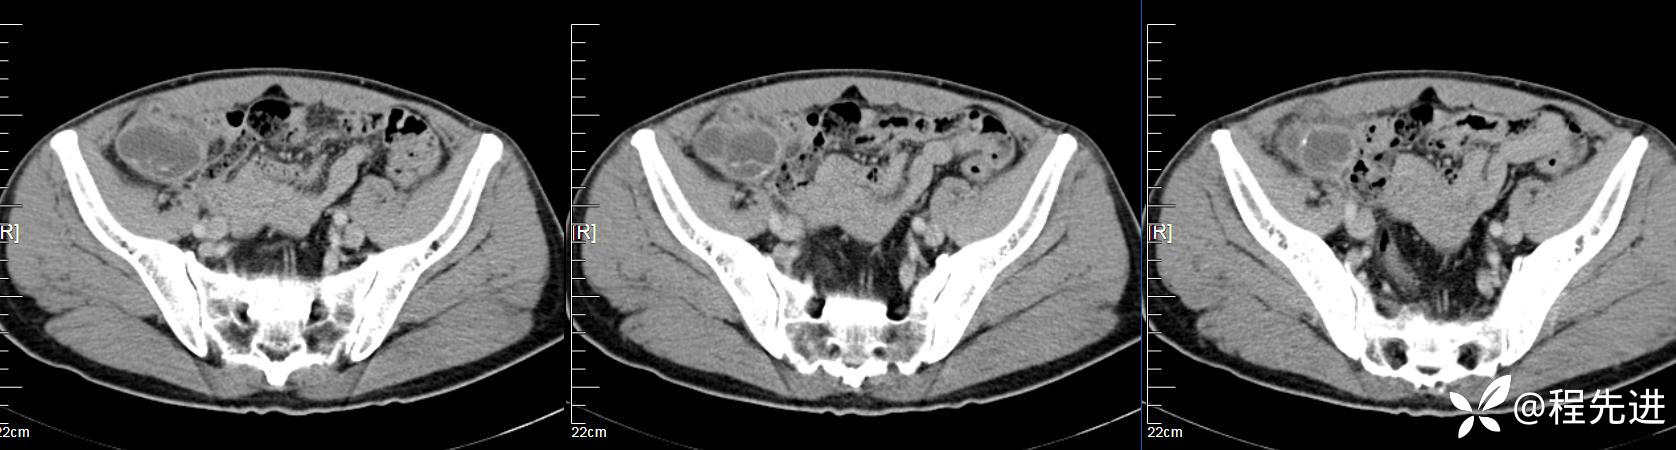

【患者信息】:男,61岁

【现病史及既往史】:右下腹部疼痛伴腹胀2天

【影像检查】